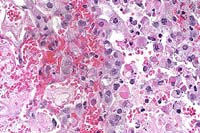

Case 16-2. Lung. There is necrosis of a respiratory bronchiole. Alveoli contain hemorrhage and serofibrinous exudate. Several large, cytoplasmic, hypereosinophilic pox inclusions are in the sloughing bronchiolar epithelium. 40X

1. Lung: Bronchopneumonia, necrotizing, subacute, multifocal, severe, with type II pneumocyte hyperplasia, necrotizing vasculitis, and eosinophilic intracytoplasmic inclusion bodies, BALB/c mouse, rodent.

2. Lymph node, mediastinal: Hyperplasia, lymphoid, follicular and paracortical, mild, with plasmacytosis.

Conference Note: Tissue sections that had been immunohistochemically stained for poxviral antigen were viewed in conference. Viral antigen was demonstrated in intracytoplasmic inclusions in numerous cell types, including bronchiolar epithelial cells, alveolar macrophages and pneumocytes, and smooth muscle cells. Electron micrographs also demonstrated typical pox virions within the cytoplasm of numerous cells.